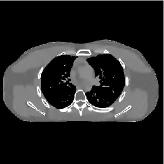

This section compares the reconstruction quality and runtime among the proposed MBIR method, PWLS-ST-, and other three MBIR methods, PWLS-EP, PWLS-DL, and PWLS-ST-. Table I shows that, for both 2D and 3D sparse-view CT reconstructions of the XCAT phantom, the proposed PWLS-ST- model outperforms PWLS-EP and PWLS-ST- in terms of RMSE. In addition, PWLS-ST- using a square transform (of size ) achieves lower RMSE than PWLS-DL using an overcomplete dictionary (of size ) for 2D sparse-view reconstructions. Fig. 3(a) and Fig. 4 show the reconstructed images for 2D and 3D phantom experiments, with different reconstruction models and different number of views. (See the corresponding error maps in the supplement.) The proposed PWLS-ST- consistently gives more accurate image reconstructions compared to other MBIR methods. Specifically, PWLS-ST- has smaller errors in the heart region (see zoom-ins in Fig. 3(a)) of 2D reconstructions than PWLS-DL and PWLS-ST-. In addition, compared to PWLS-ST-, PWLS-DL and PWLS-ST- have some ringing artifacts around the edges with high transition, e.g., edges between air and soft tissues. (See a comparison of profiles of PWLS-ST- and PWLS-ST- in the supplement.) In particular, PWLS-ST- and PWLS-DL give more visible ringing artifacts for 2D reconstruction from fewer views, and PWLS-ST- has these ringing artifacts for 3D reconstructions regardless of the number of views (see zoom-ins in Fig. 4). Table II reports runtimes of different MBIR methods in reconstructing the -views XCAT phantom scan. (FBPConvNet is a non-MBIR method and its runtime for processing a image is approximately one second with a TITAN Xp GPU.) While providing better reconstruction quality, the proposed Algorithm 1 of PWLS-ST- has shorter runtime compared to the algorithms of PWLS-DL and PWLS-ST- in Section III-A. Similar to the PWLS-EP algorithm, the reconstruction time of the PWLS-DL, PWLS-ST-, and PWLS-ST- algorithms can be further reduced by using ordered subsets [51].

![]() |

| (a) 2D fan-beam CT experiments |

| (b) 3D axial cone-beam CT experiments |